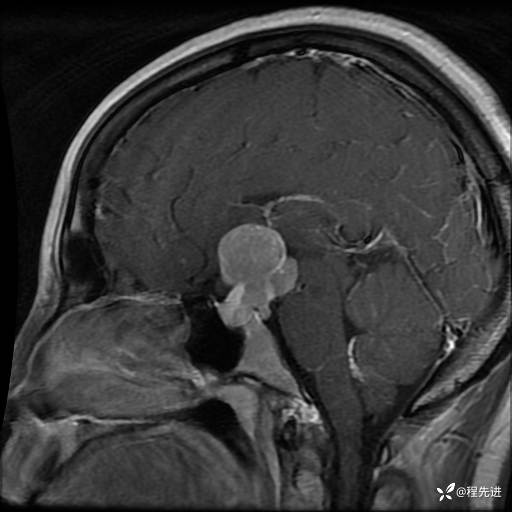

MRI平扫+增强:

T1+C: